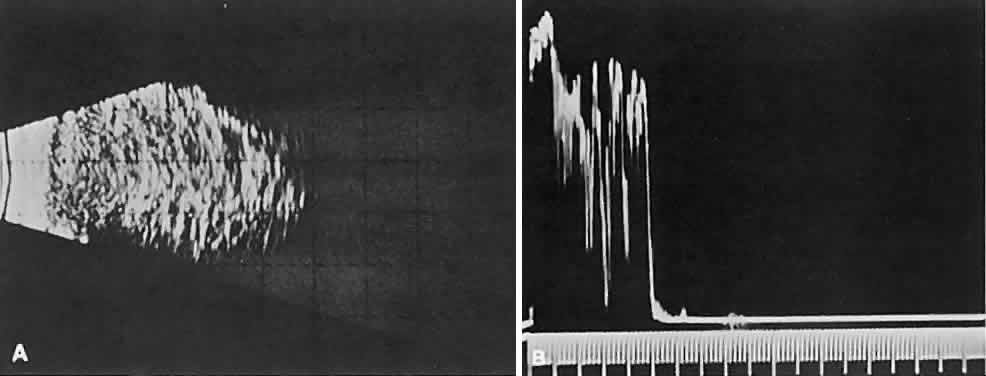

cellular tumors (see Fig. 1C). Compressibility of the lesion also is a valuable echographic finding.  Fig. 9. A. B-scan echography shows marked internal acoustic heterogeneity and lack

of circumscription. B. Quantitative A-scanning shows a corresponding pattern. High-amplitude

spikes are reflected from the vessel-lumen/cell-cluster interfaces within

the tumor. Fig. 9. A. B-scan echography shows marked internal acoustic heterogeneity and lack

of circumscription. B. Quantitative A-scanning shows a corresponding pattern. High-amplitude

spikes are reflected from the vessel-lumen/cell-cluster interfaces within

the tumor.